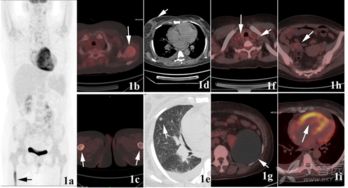

惡性腫瘤細胞由于代謝旺盛而對葡萄糖的需求增加,因此18FDG后,大多數腫瘤病灶會(huì )表現為對18FDG的高攝取,因此可應用18FDG

PET-CT顯像可早期發(fā)現全身腫瘤原發(fā)及轉移病灶,準確判斷其良、惡性,從而正確指導臨床治療決策。但是18F-FDG有著(zhù)放射性核半衰期,這就總讓受檢者們擔心,做完P(guān)ET